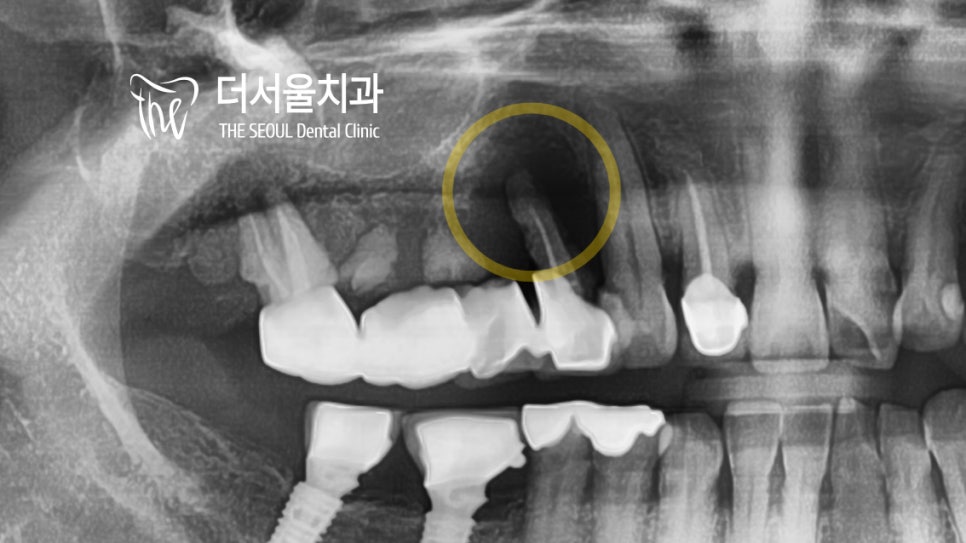

파노라마 및 육안 관찰로

환자의 상태를 확인을 했습니다.

평소 10번대 치아들이 많이 흔들려서

제대로 된 진료를 받고 싶다던 환자분,

오래된 브릿지 보철로 염증이 나타나 있었습니다.

사실 이곳은 큰 문제가 되지 않았습니다.

흔들리는 곳을 발치한 후

수술을 통해 고정체를 심어주면 되는 일이죠.

문제는 반대편에 존재하고 있었는데요.

20번대 치아를 보면 다트를 꼽아놓은 듯

주변 조직이나 치축, 방향들을 고려하지 않고

그냥 심어놓은 고정체를 확인할 수 있습니다.

정말.. 같은 의료진이지만 화가 나더라고요..ㅎㅎㅠㅠ

이렇게 삐뚤게 심어진 것은

염증이 생기기 쉽고 잘 부을 수 있습니다.

또한 추후에 있을 A/S가 어려워지게 되죠.